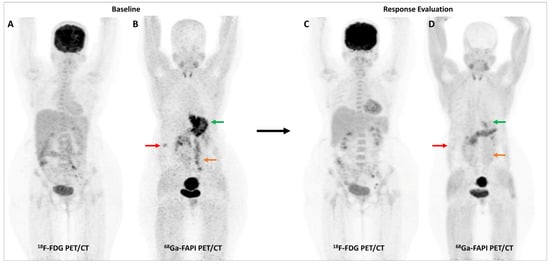

Activation of CAFs, particularly in the early development phase, leads to FAP overexpression both in tumor cells and the surrounding stromal component in CRC and other GI malignancies [72]. A higher degree of FAP expression is associated with higher tumor grade, invasiveness, and poor prognosis in CRC [73]. The first real-world clinical experience with FAP-targeted PET imaging (using either [68Ga]Ga-FAPI-04 or [68Ga]Ga-FAPI-46) in lower GI tract malignancies was reported by a German group. They found significant tracer uptake in anal cancer and liver metastases, with the TBR of most lesions being greater than 3. TNM staging was altered in 50% of the treatment-naïve patients and additional findings were picked up in 47% of patients with metastases. FAPI PET/CT improved TVD in a majority of patients being planned for radiotherapy (RT) [74]. Kömek et al. performed a head-to-head comparison of [68Ga]Ga-FAPI-04 and FDG PET/CT in 39 CRC patients. They found that FAPI PET/CT had higher sensitivity and specificity in the detection of primary lesions and lymph nodal metastases [75]. Pang et al. compared the diagnostic performance of [68Ga]Ga-FAPI-04 and FDG PET/CT in 35 patients with CRC, gastric and duodenal cancers. Overall, FAPI PET/CT had better sensitivity than FDG PET/CT for the detection of primary tumors (100% vs. 53%, respectively, p = 0.004), nodal (79% vs. 54%, p = 0.001), and distant metastases (89% vs. 57%, p = 0.001). FAPI PET/CT led to upstaging of the clinical TNM stage in 21% of the treatment-naïve patients [76]. Lin et al. reported the additional utility of [68Ga]Ga-FAPI-04 PET/CT in monitoring response to treatment in gastric carcinoma [77]. One such demonstrative case of gastric cancer is presented in Figure 3 and Figure 4.

Figure 3.

FDG and [68Ga]Ga-FAPI-04 PET/CT images in a 42-year-old woman with biopsy-proven gastric adenocarcinoma. The primary lesion in the stomach showed no abnormal FDG uptake ((A,C)—red arrows) with intense [68Ga]Ga-FAPI-04 tracer avidity ((B,D)—green arrows). FAPI PET/CT revealed a tracer avid hypodense lesion in segment V of the liver ((B,F)—green arrows), which was not picked up on FDG PET/CT ((E)—red arrow), leading to upstaging of disease. Additionally, the uterus showed no abnormal FDG uptake ((G)—red arrow) but had diffuse intense FAPI uptake ((H)—green arrow), which was interpreted as physiologic/benign uptake.

Figure 4.

Incremental role of [68Ga]Ga-FAPI-04 PET/CT over FDG PET/CT in a 42-year-old woman with metastatic gastric adenocarcinoma for post-chemotherapy response assessment. Baseline (A) and follow-up (C) FDG PET/CT scans did not reveal significant abnormal tracer uptake in the primary and metastatic lesions. Baseline [68Ga]Ga-FAPI-04 PET/CT (B) showed tracer avid gastric primary (green arrow), abdominal lymph nodes (orange arrow), and solitary liver metastasis (red arrow). Post-chemotherapy [68Ga]Ga-FAPI-04 PET/CT (D) demonstrated minimal tracer avidity in the gastric primary (green arrow) with resolution of tracer avidity in the abdominal lymph nodes (orange arrow) and liver lesion (red arrow), suggesting a favorable response to treatment.